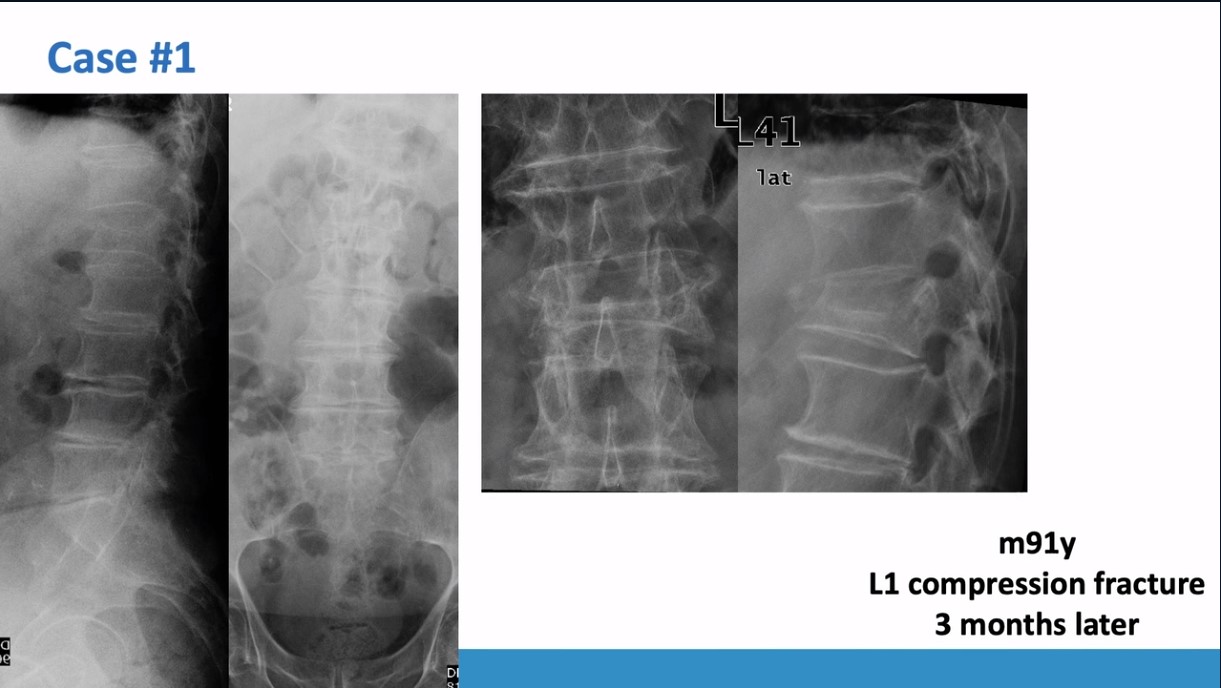

Winglet Journal Club – #017: Osteoporotic Thoraco-Lumbar Fractures of the Spine - The OF Classification

Clinical Evaluation of the Osteoporotic Fracture Treatment Score (OF-Score): Results of the Evaluation of the Osteoporotic Fracture Classification, Treatment Score and Therapy Recommendations (EOFTT) Study (Ullrich et al., 2023)